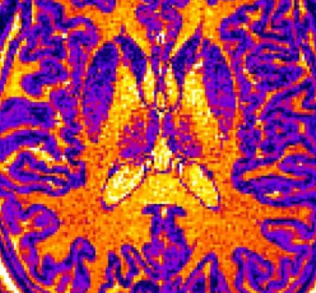

像这样的MRI图像通过机器学习计算机算法进行筛选。该算法基于大脑某些区域的厚度,体积或表面积的细微但统计上重要的差异,学会了识别非患者,诊断为自闭症的患者和诊断为精神分裂症的患者的大脑。该工具可能有助于使将来的心理健康诊断更加客观,而不是仅仅依靠患者及其家人的陈述。图片来源:CC-BY /东京大学小池真辅